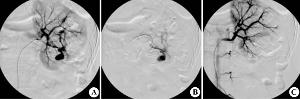

肾动脉造影为最可靠的检查方法可直接显示动脉壁的囊状膨出或梭形扩张,单发或多发可大可小,部分有动静脉瘘时,可见肾静脉早显,供血动脉有代偿性增粗并扭曲。